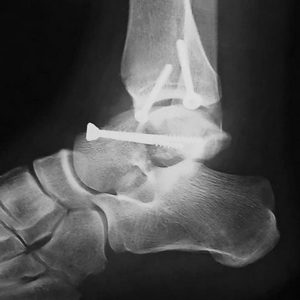

Проведение остеосинтеза

При наличии серьезного смещения отломков (от 1 см), нарушения целостности кожного покрова, дополнительных подвывихов и вывихов в суставных сочленениях, а также в ситуациях, когда закрытая репозиция не возможна, проводят оперативное лечение перелома таранной кости. Рекомендуется осуществлять хирургическое вмешательство не позднее 8 часов от момента получения травмы.

Хирургические операции выполняются по различным методикам:

- использование стержневого устройства, удерживающего спицы, по типу аппарата Илизарова позволяет закрепить костные отломки относительно друг друга, контролируя расстояние между ними;

- при классическом остеосинтезе для сопоставления отломков применяются стягивающие винты или мини-пластины;

- если выполнить реконструкцию кости не удается в связи с раздроблением ее на мелкие части или при развитии выраженного некроза костной ткани, то хирурги в таких случаях проводят артродез. Подобное вмешательство заключается в полном удалении поврежденных образований с соединением оставшихся целыми костей стопы. Необходимо отметить, что подвижность голеностопа при операции существенно снижается.

По завершению любого вида оперативного вмешательства, на стопу и голеностопный сустав накладывается фиксирующая повязка. Если у пациента использовался стержневой аппарат, то он сам выполняет функцию иммобилизации ноги.